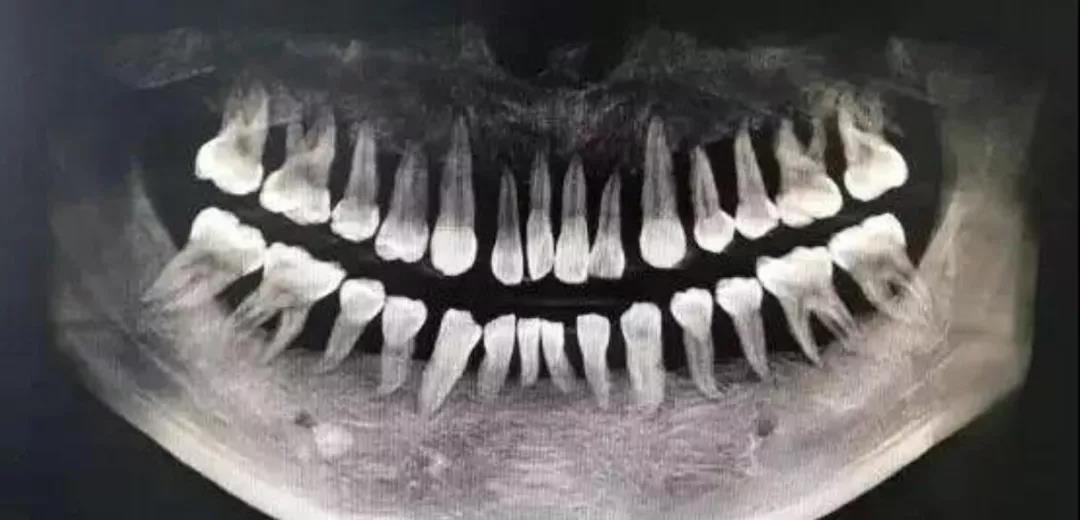

一名90后姑娘,轻度牙周炎6年发展为重度,上半口牙全部松动被拔光,而拔牙只是第一步,她还得种牙,要花费十五六万元。

杭州25岁小伙患重度牙周炎,整口牙松动明显,牙齿状况堪比80岁的老太太,同样面临全口牙拔除的困境……

此外,我国六成左右的青少年有牙结石,其中12岁青少年的牙龈出血率达58.4%;35岁以上成年人,牙周健康率不到10%,35~44岁组牙龈出血率达87.4%,牙结石检出率达96.7%。